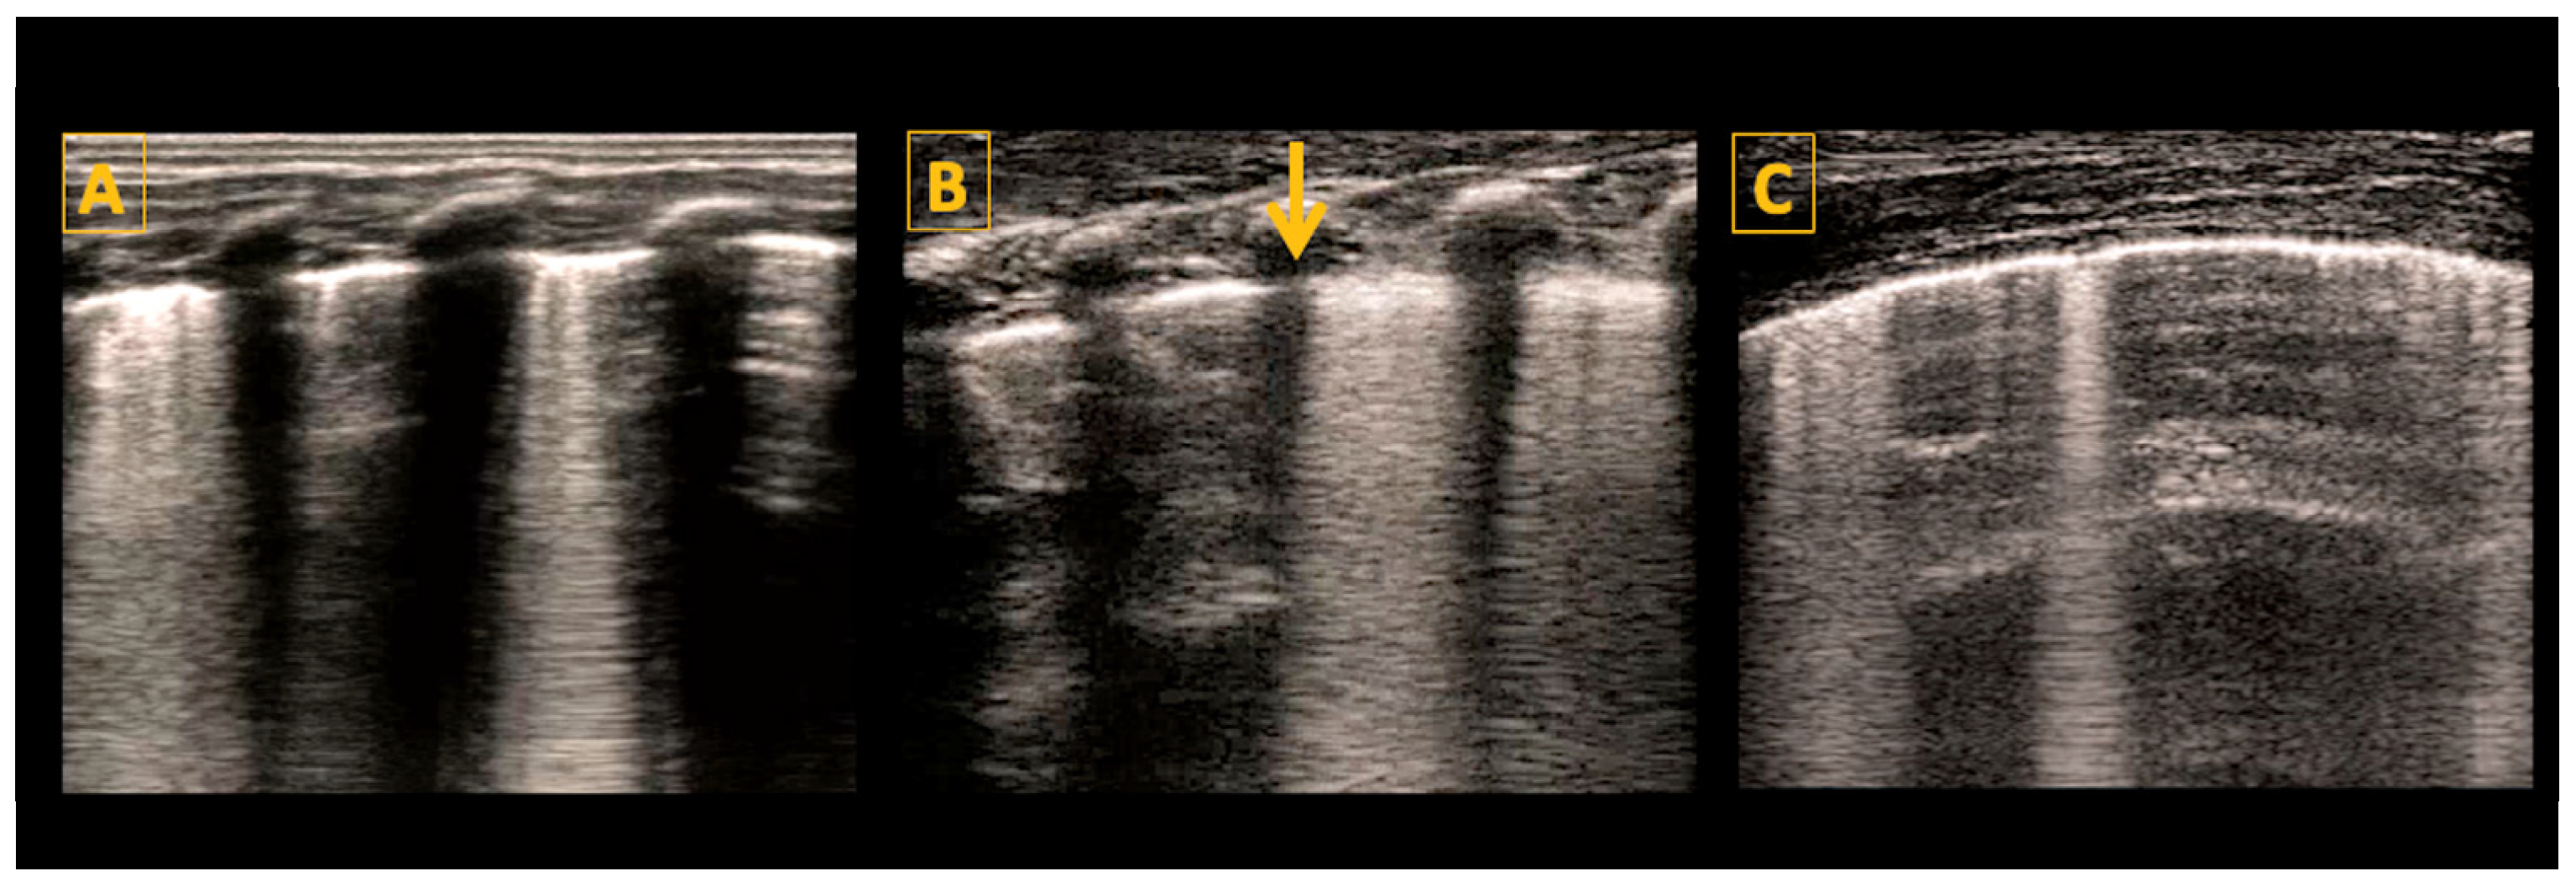

5.4.1. A-Lines

5.4.2. B-Lines

5.5. Consolidations

5.6. Pleural Effusion

- Meconium Aspiration Syndrome (MAS)

- Transient Tachypnea of Newborn (TTN)

- Pneumothorax